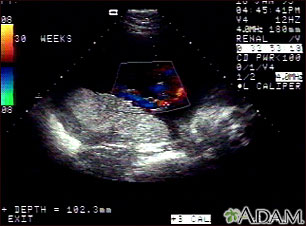

This is a normal color Doppler ultrasound of the umbilical cord performed at 30 weeks gestation. The cord is the colored area in the middle of the screen, with the different blood vessels represented by different colors. There are normally three vessels in the cord, two arteries and one vein. The umbilical cord is connected to the placenta, located in the middle left of the image.